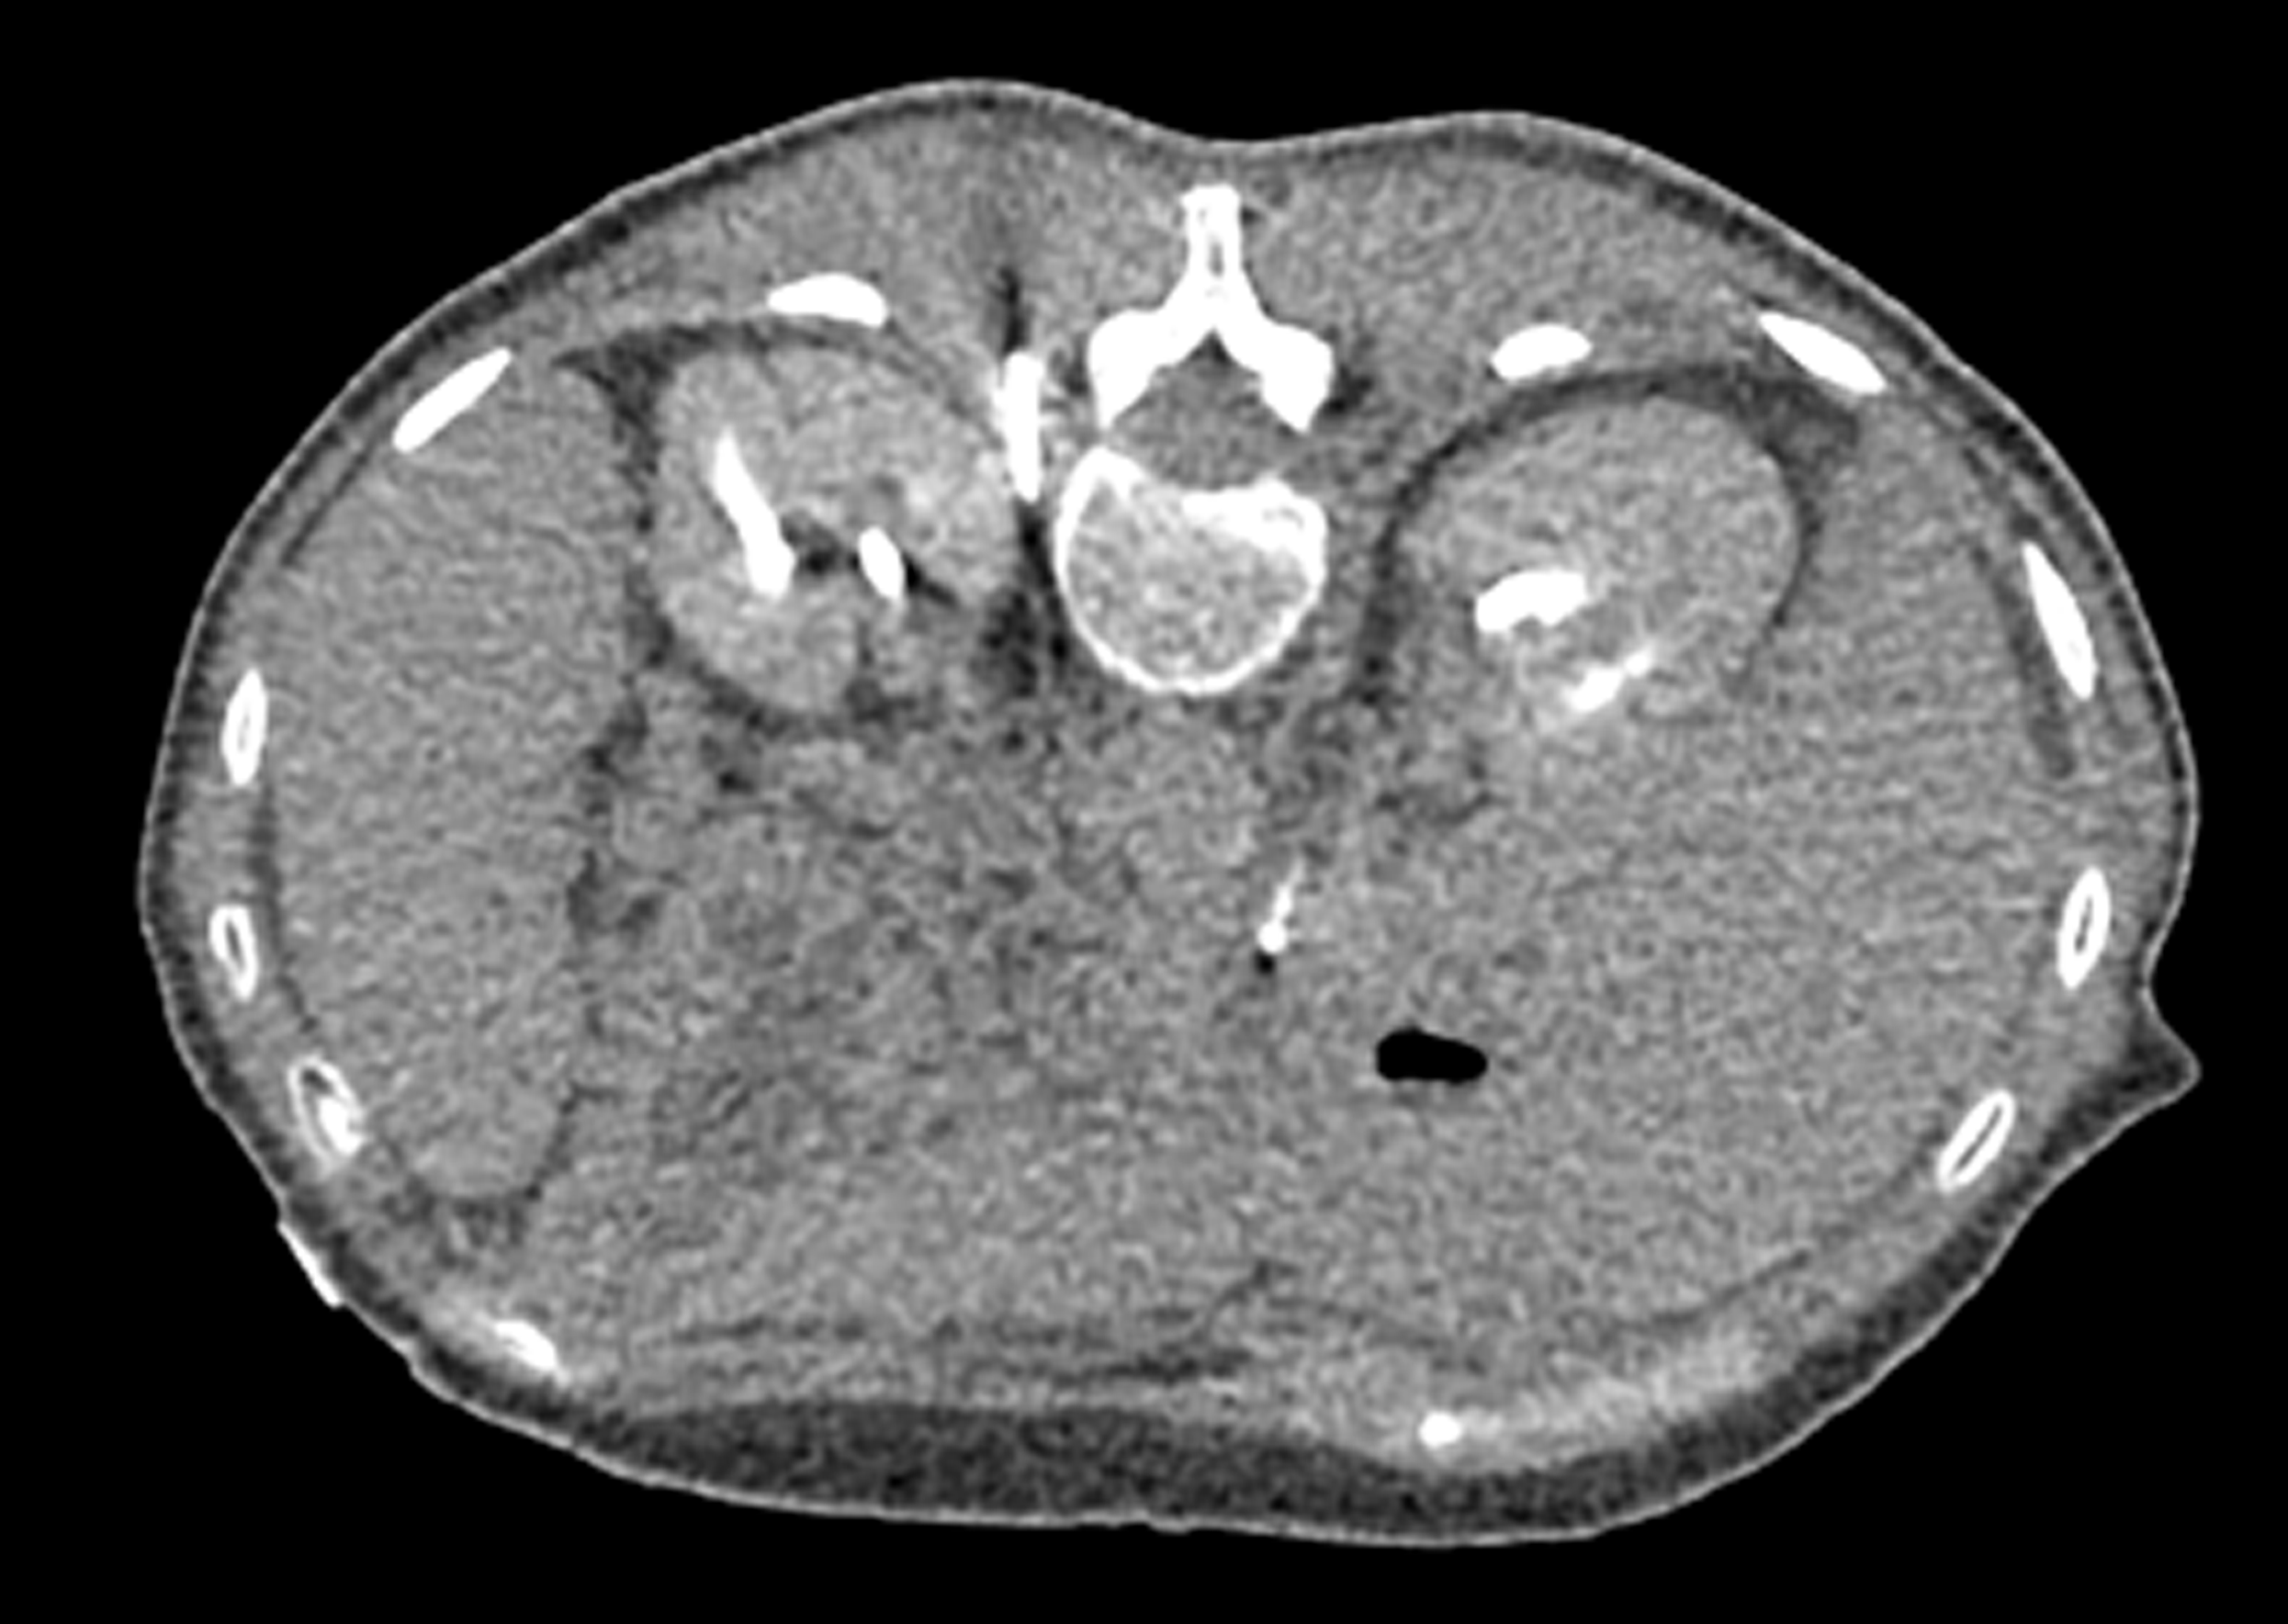

MRI image from Chary cryoneurolysis case MRI image from Chary cryoneurolysis case

Celiac Plexus Cryoneurolysis Utilized to Treat Abdominal Pain from Pancreatic Cancer

A 79-year-old man presented with abdominal pain radiating to his back. He was referred to Interventional Radiology by his Medical Oncologist for a ‘celiac plexus block.’ Two IceRod™ 1.5 CX needles were placed along the course of the celiac plexus bilaterally. The patient experienced mild orthostatic hypotension in the recovery area, a typical transient phenomenon with this treatment. The patient was seen in post-operative clinic one week after the procedure. Pain was down to 3/10 (VAS) from 8/10 (VAS) pre-op with improved appetite, better sleep, and reduced constipation. The pain relief typically last approximately 6-12 months, and the procedure can be repeated should the pain return.

Robert Evans Heithaus, MD I Vascular and Interventional Radiologist University of Florida I Gainesville, FL